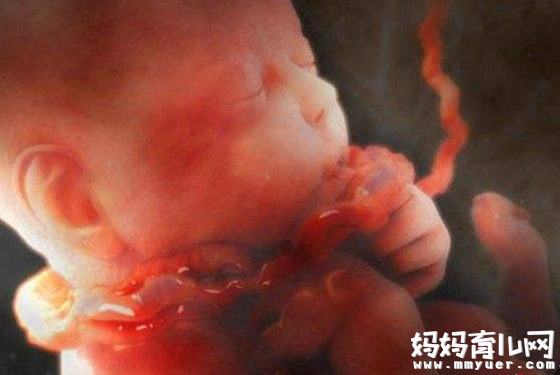

怀孕28周胎儿真实图片

由于身体新陈代谢消耗氧气量加大,活动后容易气喘吁吁。腹部向前挺得更为厉害,所以身体重心移到腹部下方,只要身体稍微失去平衡就会感到腰酸背痛或腿痛。心脏的负担也在逐渐加重,血压开始增高,静脉曲张、痔疮、便秘这些麻烦,接踵而至地烦扰着孕妈妈。